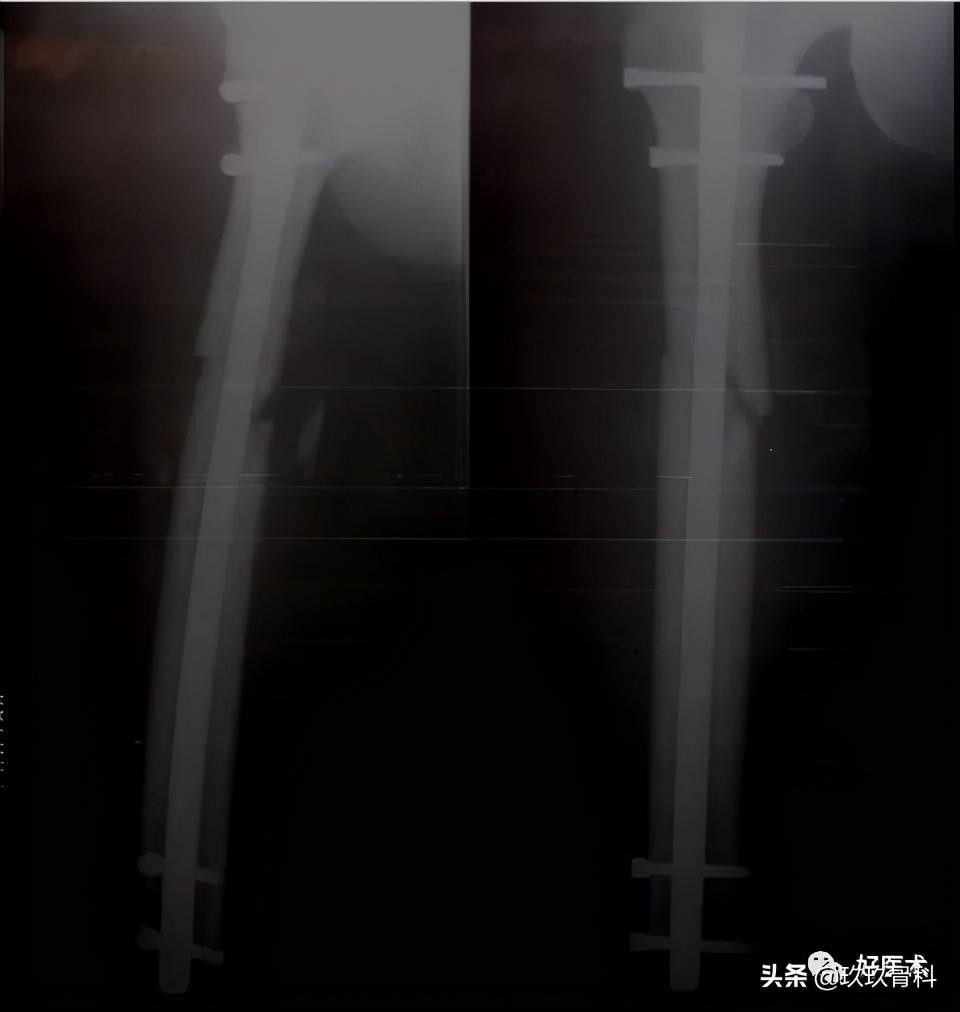

(七)延迟&不愈合手术的复位技术

1.延迟手术可能遇到的问题

- 轴向畸形(短缩、成角和或移位)

- 肉芽组织长入

- 早期骨痂

- 骨折断端硬化,髓腔封闭

- 骨质疏松

2.术中可能出现的问题

- 扩髓器和髓内钉偏斜→髓内钉穿出皮质

- 成角畸形→牵开器

- 断端错位→Poller钉 钢板固定

3.防止力线异常的方法

- 近段-进针点正确

- 远端-髓内钉位于髓腔中心

- 近端或远端干骺端骨折